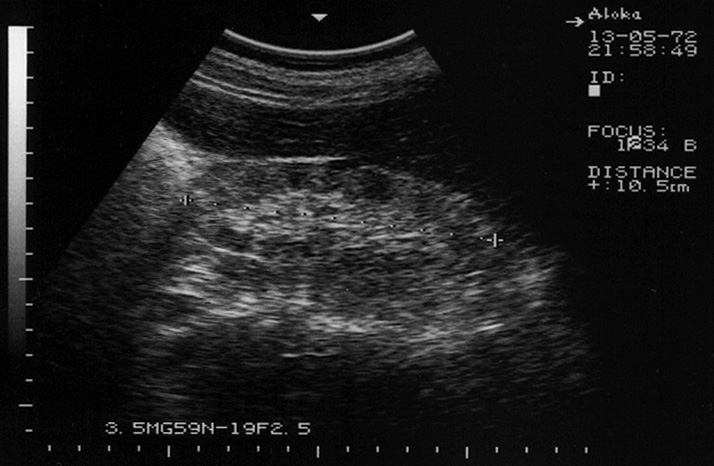

Амилоидоз почек. Renal amyloidosis

Диагноз доказан морфологически.

amyloid2.jpg